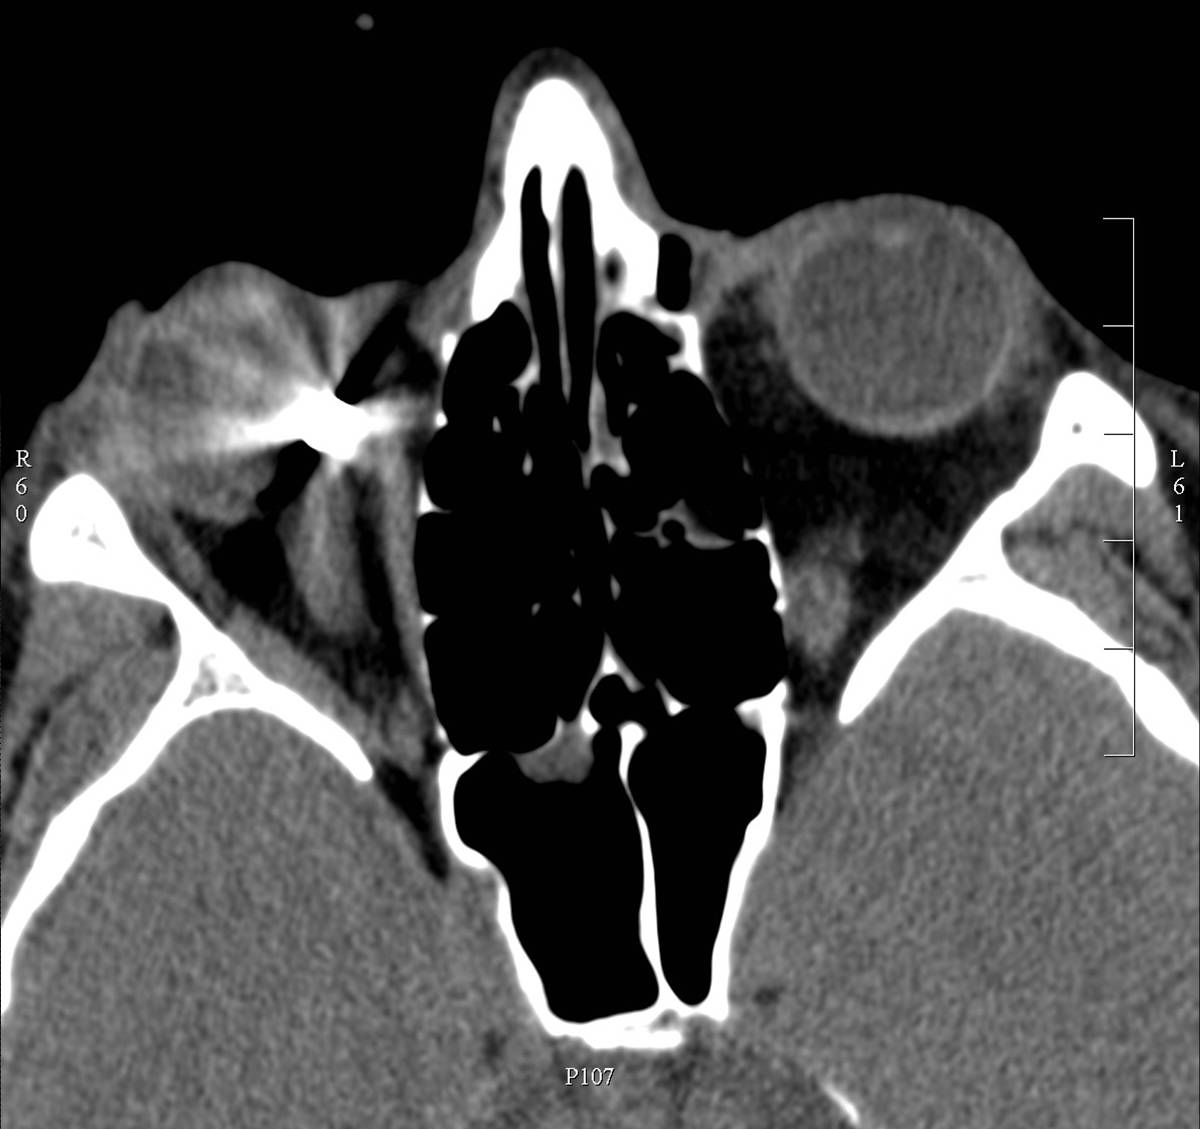

2. image: Axial view of the orbits in noncontrast CT. Metallic foreign body (indication for CT) in the medial part of the right orbit.